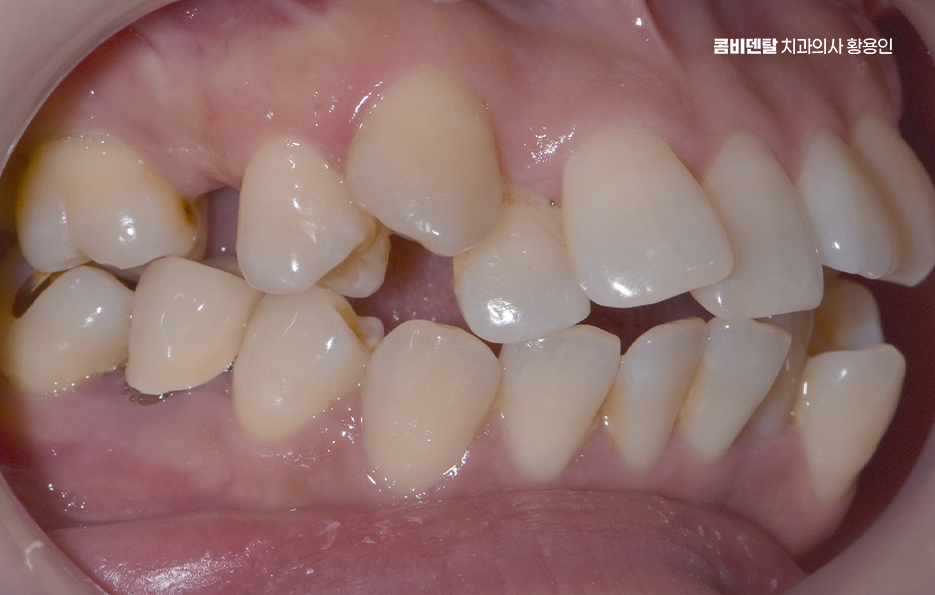

출처 아카이브 열기거울을 보다 보면 늘 시선이 먼저 가는 게 앞니였어요, 남들이 보기엔 별로 티 안 나는 거라고 생각하기도 했지만 항상 앞니가 조금 틀어져 있다는 걸 의식하게 됐고, 사진 찍을 때도 살짝 미소만 짓게 되는 이유가 그거였어요, 사실 예전부터 교정을 해야겠다는 생각은 있었지만 앞니만 살짝 신경 쓰이는 정도라서 큰 결심까지는 안 갔었고, 그냥 참고 살면 되지 뭐 이런 식으로 넘기곤 했는데, 어느 날 치과에 전반적인 치열이 생각보다 안 좋은 편이라고 말씀하시는 걸 듣고는 좀 충격을 받았어요, 제 눈에는 앞니만 문제였지 전체적인 교합이 그렇게 문제인 줄은 몰랐거든요. 정확한 상태를 알기 위해 정밀 검사를 받았는데, 앞니가 살짝 겹쳐 있는 건 물론이고 아래쪽 어금니는 바깥쪽으로 기울어져 있어서 씹는 힘이 한쪽으로만 가고 있고, 전반적으로 치아 배열이 삐뚤빼뚤하게 늘어선 상태라 기능적인 문제도 고민할 수 밖에 없었어요

예를 들어 송곳니가 제자리를 찾지 못해 앞으로 튀어나와 있거나, 소구치가 비틀어져 있으면 그 힘이 앞니로 전달되면서 앞니가 서로 겹치고 밀리는 형태가 되는데 즉, 보이는 앞니가 문제처럼 보일 뿐, 실은 그 뿌리를 뒤에서 밀어내는 힘들이 원인이 될 수 있기 때문에 앞니만 간단히 밀어넣는 식의 교정은 일시적인 변화만 줄 수 있고 전체 치열을 다 잡아줘야 안정적인 결과를 만들 수 있었어요.

전체적인 부정교합을 교정하려면 먼저 교합 상태, 즉 위아래 치아가 어떻게 맞물리는지를 확인해야 하는데 위턱과 아래턱이 서로 자연스럽게 맞물리지 않고, 삐뚤거나 앞니가 부딪치거나, 아래턱이 더 튀어나와 있는 경우가 많이 있었어요

또 턱의 비대칭이나 턱관절 이상이 있는지까지 함께 체크해야 하는데 이런 부분을 모두 포함해서 앞니 틀어짐 교정 치료 계획이 세워져야 하며 얼굴의 중심선과 턱의 위치까지 고려한 계획이 필요한 거예요.